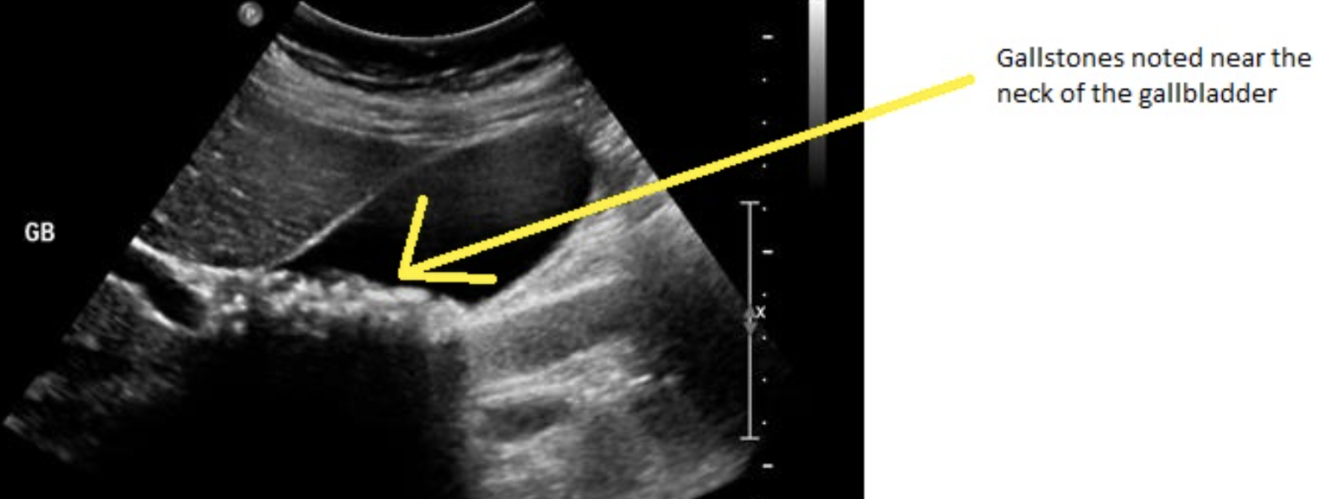

When trying to diagnose a patient with acute pancreatitis we need to rule out the most common cause. What is the first line imaging used for this?

4 - ultrasound

• reliably identifies gallstones and biliary dilation